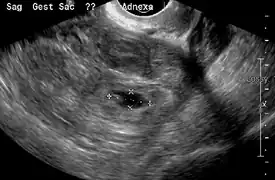

An ultrasound showing a gestational sac with fetal heart in the fallopian tube has a very high specificity of ectopic pregnancy. Transvaginal ultrasonography has a sensitivity of at least 90% for ectopic pregnancy.[4] The diagnostic ultrasonographic finding in ectopic pregnancy is an adnexal mass that moves separately from the ovary. In around 60% of cases, it is an inhomogeneous or a noncystic adnexal mass sometimes known as the "blob sign". It is generally spherical, but a more tubular appearance may be seen in case of hematosalpinx. This sign has been estimated to have a sensitivity of 84% and specificity of 99% in diagnosing ectopic pregnancy.[4] In the study estimating these values, the blob sign had a positive predictive value of 96% and a negative predictive value of 95%.[4] The visualization of an empty extrauterine gestational sac is sometimes known as the "bagel sign", and is present in around 20% of cases.[4] In another 20% of cases, there is visualization of a gestational sac containing a yolk sac or an embryo.[4] Ectopic pregnancies where there is visualization of cardiac activity are sometimes termed "viable ectopic".[4]

A pregnancy not in the uterus.[31]